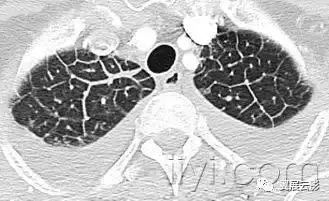

二十、铺路石征:

CT扫描:铺路石征表现为磨玻璃影背景上小叶间隔和小叶内线增厚,呈现不规则的铺路石征。铺路石征常与相对正常肺组织分界清楚,边缘规则。该征象最早报道于肺泡蛋白沉积症,也可见于其他类型同时累及肺间质和肺实质的弥漫性肺疾病,包括脂性肺炎。